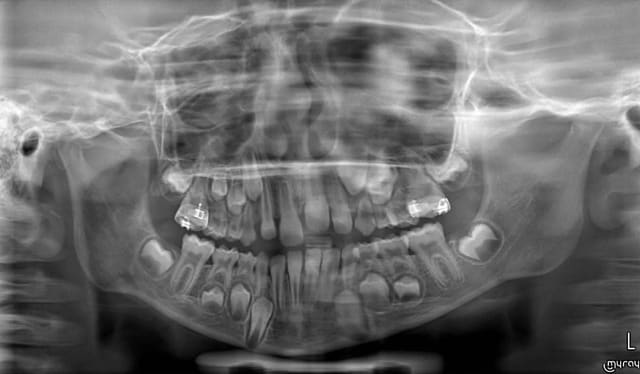

au vu des pano (seul element dont je dispose) je trouve que la vitalité pulpaire des 11 et 21 est très douteuse.

ci dessus les pano en fevrier 2015 et septembre 2015